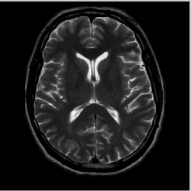

The comparison of the methods in the context of random sampling with 20% of the samples retained in the absence of noise is shown in Fig. 4. The regularization parameters of all the algorithms have been optimized to yield the best signal to noise ratio (SNR). The SNR and the peak SNR (PSNR) that are used for the comparisons in this paper are computed as

We observe that the proposed non-local algorithm provides better preservation of edge details and minimize patchy artifacts as seen in TV reconstructions. The quantitative comparisons of different methods on more MR images in the absence of noise using 5 fold random sampling operator are reported in Table III. We observe that the NLS scheme provides a consistent 2-4 dB improvement over the other methods in most cases.

Figure 4: Comparison of the algorithms in the absence of noise. We consider the recovery of a 256×\times256 MRI brain image from 20% of its Fourier samples, acquired using a random sampling pattern shown in (e) using non-local shrinkage scheme (NLS), DLMRI and local TV (TV). The reconstructions are shown in (b)-(d). The corresponding error images, scaled by a factor of 5 for better visualization, are shown in the bottom row. The reconstructions show that the NLS scheme is capable of better preserving the edges and details, resulting in less blurred reconstructions.